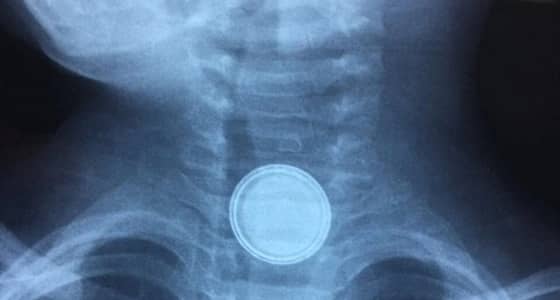

بالصور.. طفل يبتلع " بطارية حديدية " في عرعر